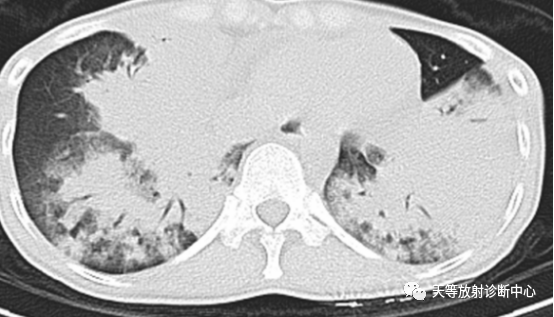

▲结核球型:具有尖角及刀切改变。

▲支气管型,沿支气管血管束向肺内弥漫性分布,呈斑片状、片状及小结节状分布,可见树芽征。